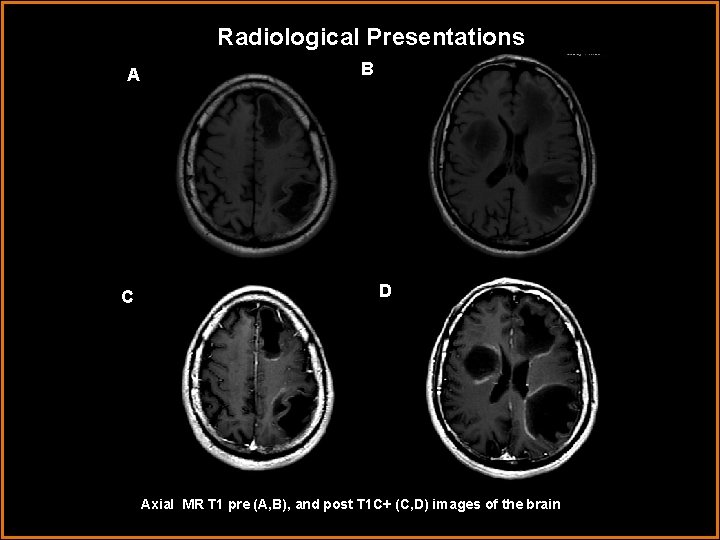

Radiological Presentations A C B D Axial MR T 1 pre (A, B), and post T 1 C+ (C, D) images of the brain

Radiological Presentations A B C D (A, B) Axial MR T 1 precontrast images demonstrate T 1 hypointense and isointense lesions within the periventricular and subcortical white matter. (C, D) Axial postcontast T 1 C+ images of the brain demonstrate incomplete contrast enhancement or “horseshoe” enhancement ( ) of hypointense lesions within the periventricular and subcortical white matter